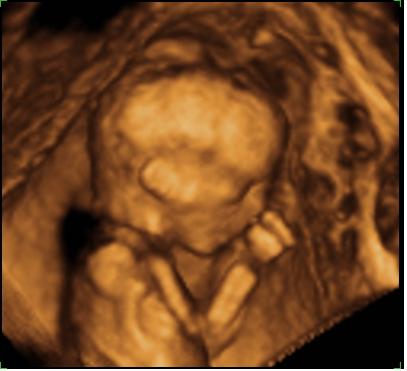

Csupa szép történet után leírom az enyémet is,ami nem olyan szép és nem is tökéletes,de az enyém és azt hiszem nagy könnyebség lesz majd megszabadulni tőle.1997.dec 27-e volt,pont amikorra ki voltam írva. Délután már éreztem enyhe és rendszertelen időközönként fájásokat,de nem gondoltam,hogy szülök. Az esti film alatt ezek rendszeressé és erősekké váltak,majd egyre sűrűsödtek. Első baba révén hívtam is a dokimat,nehogy a végégn még megszüljek,mielőtt beérnék. Éjfél volt,mire a korházba értem. Az ügyeletes orvos fogadott,aki becsmérlő megjegyzéseket tett,miszerint nem úgy nézek ki,mintha tényleg fájásaim lennének,szerinte menjek haza aludni.Apukám hosszasan győzködte,hogy messziről jöttünk,az utak le vannak fagyva és hát mégiscsak fájássaim vannak. Megvizsgált és azt mondta,hogy másfél újnyi a méhszáj,bent alhatok az osztályon,ha ennyire ragaszkodom hozzá,de előtte menjek a vajudóba,és rámcsatolják a gépet,ami méri az összehúzódásokat.Na ez volt a szerencsém,ott ugyanis fogadott szülésznőm és egy fiatal kezdő lelkes dokinő fogadtak és hát a mért fájások engem igazoltak,még akkor is,ha nem ordítoztam fájdalmamban a portán befelé jövet.Szóltak is a férjemnek,hogy öltözzön be,mert szülünk.Közben megérkezett a fogadott orvosom,amitől nagyon megkönnyebbültem.Azt mondta,minden ok,és reggelre meglesz a babám.Lezuhanyoztam,és kérésemre eltekintettek a beöntéstől és a borotválástól is.Sétalgattunk a folyosón,és közben telefonon hivogattam a családot,barátokat,szóval itt még birtam a dolgot.Állandóan pisislni jártam.Megvizsgált a doki és úgy döntött burkot repeszt,amitől majd felgyorsulnak az események.Sajna nem nagyon tágultam,még mindíg csak 2 ujnyi a méhszáj.Nagyon féltem a burokrepesztéstől,de nem éreztem semmit. A magzatvíz tiszta volt. Újabb séta kezdődött,bugyi nélkül egy lábközé szorított pelussal.Mókás volt. Nagyon furi volt,hogy sokkal kisebb lett a hasam és szinte simogattam a kisbabámat a pocakomban.Éreztem a testrészeit.Valóban gyorsultak az események,mert innentől kezdve felerősödtek a fájásaim és már nem tudtam sétálni,úgy éreztem muszáj feküdnöm.Az orvos nem volt elégedett,mert egyáltalán nem tágultam tovább,így elkezdte kézzel tágítani a méhszájam,ami leírhatatlanul fájt,közben el is hánytam magam,úgyhogy abbahagyta és bekötöttek egy infúzióban oxitocint,hogy végre táguljak.A szülésznőm végig mellettem volt,türelmes volt és szeretettel vett körül. A férjemet nem nagyon engedtem közel magamhoz.Megnyugtatott,hogy ott ül az ágyam végében,de nem akartam,hogy hozzámérjen,vagy kommunikáljon.Úgy éreztem kizökkentene a belső világomból,amiben vagyok.Most már olyan erősek voltak a fájásaim,hogy úgy éreztem,nem birom elviselni,úgyhogy a kezemet haraptam és ráztam a fejemetütemesen.Szép látvány lehetett.Így voltam csak képes némán elviselni a fájásokat. Közben eljött a reggel és én még mindíg 2 újnyi voltam,úgyhogy újabb adag oxitocint kaptam a dokimtól,aki kedves volt és biztatott.Innentől kezdve elvesztettem az időérzékemet,és nem érzékeltem a fájások közti szünetet sem csak haraptam a kezem,ráztam a fejem és abban bíztam,hogy a doki meg fog császározni.Mikor legközelebb bejött,fel is vetettem neki ezt az ötletet,hiszen úgy éreztem jártányi erőm sincs,szomjan halok és nem vagyok képes végigcsinálni.De ő azt válaszolta,hogy a fájdalom nem ok a császárra és még egy adag oxitocint kaptam.Ekkor már úgy dél körül lehetett.Innentől kezdve tényleg úgy éreztem magam,mint aki haldoklik és elviselhetetlen állandósult fájdalmat kezdtem érezni a gerincem alsó szakaszán és a medencémben. Éreztem,hogy ez valami más,olyan,amit nem szabadna éreznem,úgyhogy szóltam a szülésznőnek,meg a dokinak,de nem vették komolyan,hiszen honnan is tudnám mit kell éreznem,ha most szülök először. Megvizsgált a doki és közölte,hogy a méhszáj eltünt,szülünk.Eszméletlenül megijedtem.Nem tudom miért,de rettegtem és úgy éreztem képtelen vagyok átvonszolni magam a szülőszobába. Felmásztam az ágyra és közölték velem,hogy a következő fájásnál nyomjak. Nekem viszont egyáltalán nem voltak tolófájásaim,legalábbis semmi olyan,amiről hallottam,olvastam,csak a gerincem és a csípőm akart eltörni. Hát én csak nyomtam és nyomtam,minden fájásnál,ki tudja hányszor,mígnem rámordított a dokim,aki az egész terhesgondozás és a szülés ezt megelőző fázisában maga voltv a tökély. Azt mondta,hogy gyengül a baba szívhangja és azonnal hagyjam abba a nyomást.Majd kiabált velem,hogy mi az,hogy nem tudom megszülni a gyereket,mi lett volna velem a középkorban,mire én annyit válaszoltam,hogy nyilván belehaltam volna.Mindenki otthagyott,nagyon hosszú időnek tünt ez a magány,pedig gondolom egy perc sem lehetett.Összehívtak egy konzíliumot és egy csomó doki jelent meg a szobában. A hasamba feküdtek és préselték ki belőlem a kisfiamat én pedig azt gondoltam,hogy soha többé nem szülök,csak ezen legyek túl és a kisfiam egészséges legyen.Majd gátmetszés és vákum,nem kérdeztek,csak hallottam,hogy mi történik körülöttem.Addígra már nem hallották a baba szívhangját ésn pedig az eddigi ném a szenvedés után ordítozni kezdtem,hogy csináljanak már valamit. És aztán megszünt a világ.Délután fél 4-kor megszületet a kisfiam,azonnal felsírt és a történtek ellenére gyönyörű volt. Abban a pillanatban elfelejtettem mindent ami előtte történt.Leírhatatlan érzés volt.Ezután összevarrtak,ami nagyon fájt,szana szét repedtem a vákumtól. Bálinka 4kg 5 dkg-al jött a világra.Mindehez én 158 cm vagyok és baba náélkül 50 kg.Nem semmi,ugye?Nem csoda,hogy nem ment simán. Ezután a kutacson keresztül ultrahanngal mevizsgálták a fejét és egy cisztát,vérömlenyt találtak a fejében. A babám beékelődött a kismedencébe,ez volt az éles fájdalom és ezért nem voltak tolófájások sem. Ahogy szorította őt a medencecsont oxigénhiányos állapotba került és gyakorlatilag egy pici agyvérzést kapott. Azt mondta a doki,hogy amozgatóidegeket érinti és ha okoz majd problémát,akkor a jobb kezét és lábát húzni fogja a gyerek. Egyértelműen császározni kellett volna.Másfál évesen egy MRI-n megállapították,hogy felszívódott a vérömleny nyomtalanul. A fiam most megy harmadikba,most voltunk kontroll MRI-n,ami negatív,de a fejlődésneurológus látja sajnos a visszamaradt károsodást,máshogy terheli a jobb lábát és csúnyán,nehezen ír,rajzol. Persze ezek a tünetek laikus szemére észrevehetetlenek,és én minden nap hálát adok az Istennek,hogy ilyen szerencsésen végződött ez a kis "tévedés" a dokimtól,akit azóta sem láttam. MOst tervezzük a tesót. Ősztől mehet a babagyártás.Igen,kellett egy kis idő,hogy lelkileg úgy érezzem,képes vagyok szülni. Másik korházban és másik orvosnál tervezem mindezt.(ez a szülés a II.sz Női Klinikán történt)Sok is merősöm szült itt,mindenkinek jó tapasztalatai voltak,csakúgy mint a dokimról is. Hát én elég peches voltam.Összességében mégis a legcsodálatosabb élmény,hogy anya lettem,és vagyok lassan 9 éve.